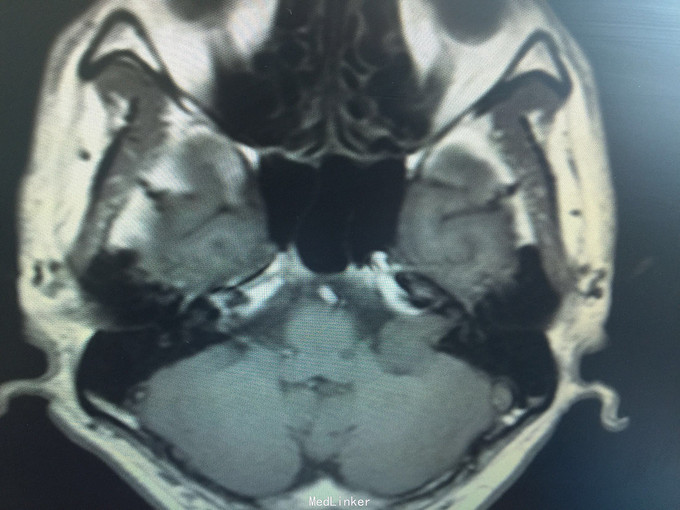

男,52岁,以“左耳鸣、听力下降1年余”入院。 现病史:1年余前看电视时出现左耳鸣、听力下降,左耳听电视声音时听不清,较右侧明显下降,未在意,之后听力下降逐渐至丧失! 既往史:既往高血压、糖尿病病史,长期吸烟病史。 家族史:无特殊!

查体:BP:150/90mmHg,心肺腹未见异常,神清语明,左耳听力丧失,无面瘫,双瞳孔等大正圆,直径约3.0mm,光敏,四肢肌力5级,肌张力正常,巴氏征R-L-。

1.左侧听神经瘤